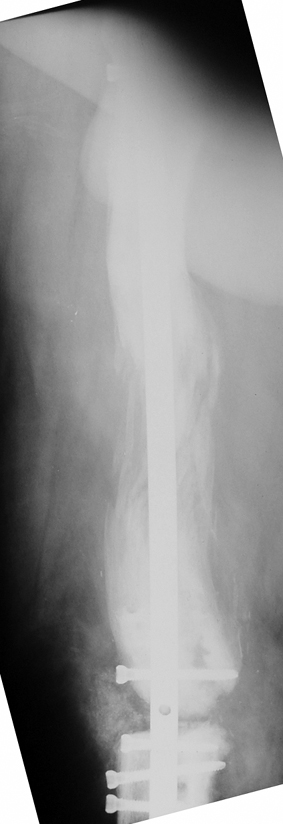

Eksternal fiksatör ile geçen süre (eksternal fiksasyon indeksi), gereken distraksiyon miktarına bağlıdır ve bu süre boyunca bazı komplikasyonlarla karşılaşılabilir. Distraksiyon dönemi sona erdikten sonra, distraksiyon süresinin iki katını aşan konsolidasyon döneminde hastalar eksternal fiksatörü zorlukla tolere edebilirler. Yeterli konsolidasyon sağlanmadan eksternal fiksatör çıkartılırsa ise kırıklar, deformite ve kısalık oluşabilir. Hastanın fiksatör ile birlikte geçirdiği sürenin azaltılması ve böylece hasta konforunun ve aktivite düzeyinin arttırılması için intramedüller çivi üzerinden uzatma yöntemi uygulanmaktadır. Bu yöntemde distraksiyon dönemi sona erdiğinde kemiğin içindeki çivi statik olarak kilitlenmekte ve eksternal fiksatör çıkartılmaktadır. Stabilizasyon intramedüller çivi tarafından sağlandıktan sonra konsolidasyon dönemi gerçekleşmektedir. Bu şekilde hem eksternal fiksatörün uzun süre kalmasından hem de erken çıkartılmasından kaynaklanan komplikasyonların önüne geçilmektedir.